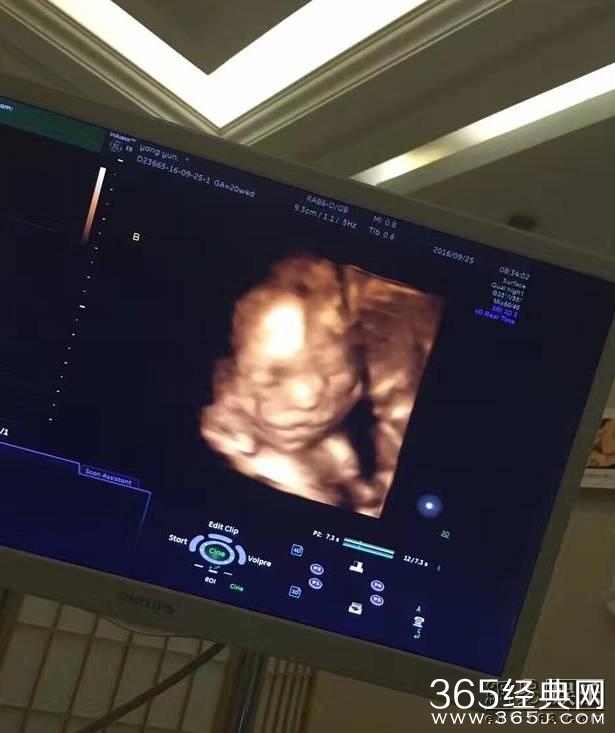

近日,杨威在微博上晒出了一张B超照片,配文字:“像谁呢,一个像我,一个像她!”

原来是家里要有新成员啦,而且一次来两个,杨云怀了双胞胎,观众为黄渤贡献了70亿票房,却只投6票给他,输给冯绍峰,心疼